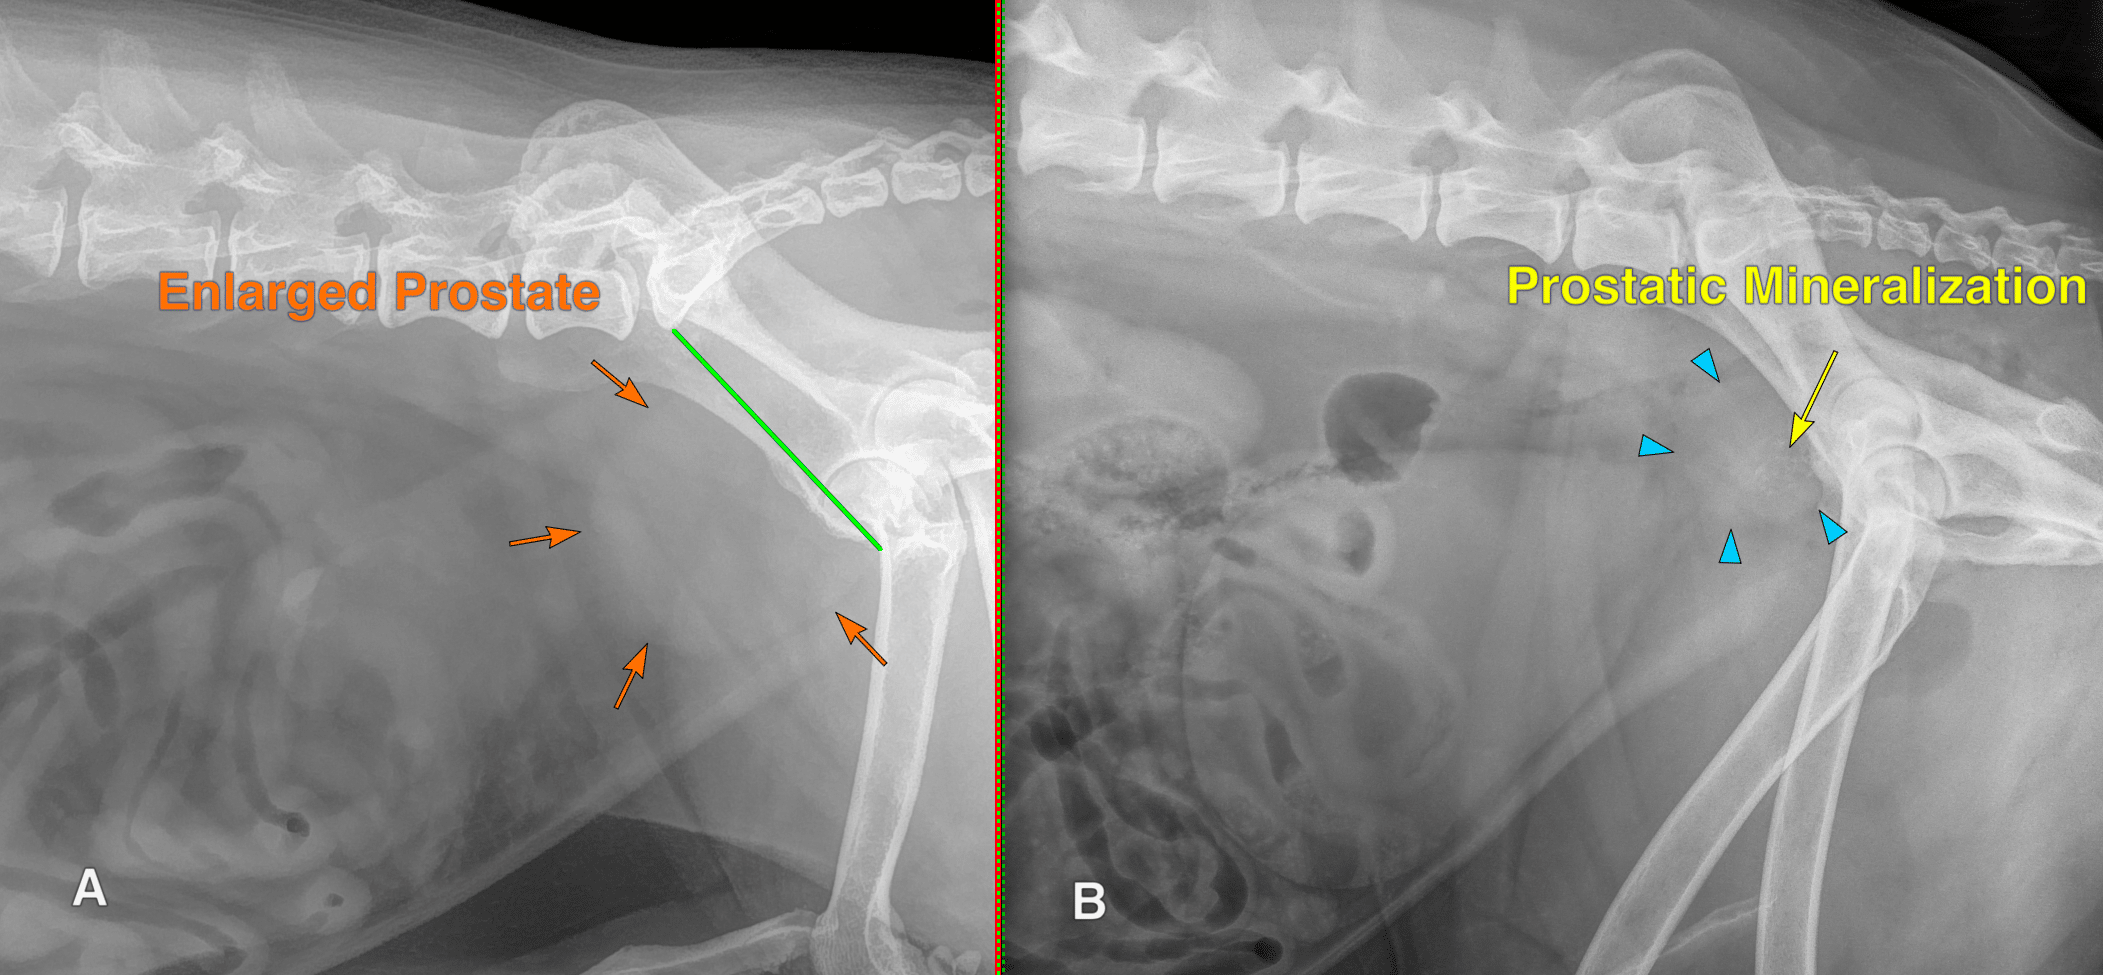

Figure 9: (A) Lateral radiograph of an intact male dog with prostatomegaly. There is a smooth, round soft tissue opacity at the pelvic inlet (orange arrows), which measures approximately 85% of the height of the pelvic inlet (green line). This patient has benign prostatic hyperplasia. (B) Lateral radiograph of a castrated male dog with an enlarged prostate (blue arrowheads) that exhibits dystrophic mineralization (yellow arrow). This patient has prostatic transitional cell carcinoma.

Neutered male dogs have a higher risk of prostatic neoplasia than intact male dogs. The most common forms of prostatic neoplasia are TCC or prostatic adenocarcinoma. The prostate gland is typically not visible at all in neutered male dogs; anecdotally, they usually measure between 1 and 2 cm in thickness. Any rounded soft tissue structure in the location of the prostate in a neutered male dog should raise some concern for prostatic neoplasia. Similar to bladder masses, mineralization of the prostate raises significant concern for cancer, with one study showing 100% positive predictive value for malignancy in mineralized prostate lesions in neutered males.4 (Figure 9)

Although the prostate gland is not technically part of the urinary system, it completely encircles the proximal urethra in male dogs. It is therefore often implicated in lower urinary tract abnormalities. As noted above, a normal prostate is generally considered to be less than 70% the height of the pelvic inlet. It should be noted, however, that the prostate gland normally increases in size with age in intact male dogs, and there is no strict pathologic delineation between a normal prostate and benign prostatic hyperplasia (BPH). It should be presumed that all intact males will develop BPH given enough time, and prostatomegaly itself should not be viewed as pathologic unless correlated with clinical symptoms. Generally speaking, there is no radiographic way to differentiate BPH from prostatitis or prostatic abscessation. (Figure 9)